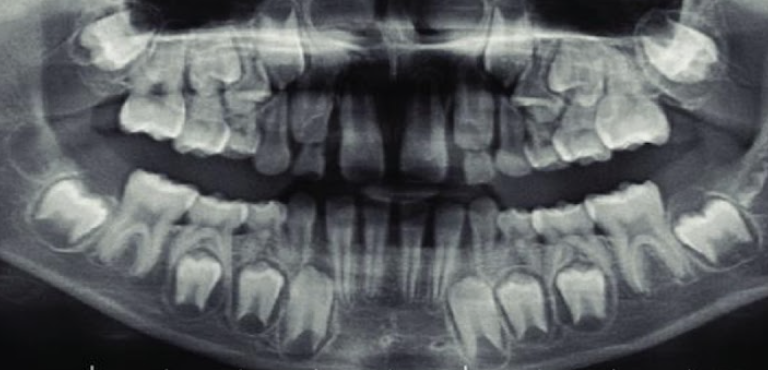

1.lower adult CI there? YES, so def 6-7

1. Upper Ad. Ci there? NO, so either 6-7 or under

Last molar crown not really formed so 6?

NOTE- THE 8’s - crown starts developing at 9 yo.